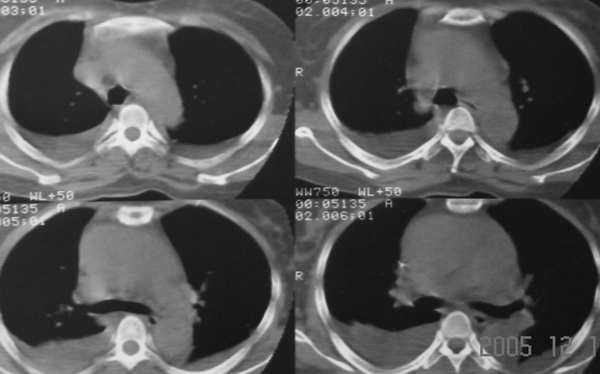

个人认为是心包积液,因为胸膜腔里的如果不包裹,易于流动,而此例病人心影周围的水是沿着心包腔的限制分布的,所以认为是心包积液

我认为,一般情况胸腔积液与心包积液并没有相关性,我们经常看到胸腔积液,但心包积液比胸腔积液要少。而这个患者心包积液较重,且发病较急,存在心包填塞的表现,右心房增大,说明回心血流受阻,肺淤血,可能会导致胸腔积液。该患者心包积液较重,建议进一步增强扫描。

“胸腔积液与心包积液”的诊断可以肯定。结合突然发病的病史,考虑:主动脉窦口破裂可能大。

“胸腔积液”的诊断可以肯定。结合突然发病的病史,考虑:主动脉窦口破裂可能大,引起心包积血。

患者急性起病,影象学表现为大量心包积液和双侧胸腔积液,心包积液密度较高,应该考虑为积血,患者没有外伤史,自发性心包积血应该想到主动脉夹层动脉瘤心包内部分破裂的可能,主动脉根部明显增粗也支持该诊断。关于胸腔积液有两种可能的解释,一是由于夹层的压力很高,造成血性胸腔渗出;另外就是由于心包填塞造成腔静脉系统压力增高,引起胸腔的渗出改变。

不知道患者有无高血压病史,高血压是造成主动脉夹层的最主要原因。

心包大量积液,双侧行腔积液,升主动脉增宽,结合突然发病,不排除主动脉夹层破裂。

回11楼,患者有高血压史.谢谢!